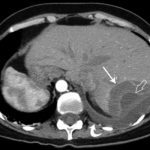

КТ

Дополнительно необходимо пройти компьютерную томографию, предпочтительно исследование с применением контрастных веществ. Компьютерная томография дает возможность установить наличие гемангиомы в 65-70% случаев.

Магнитно-резонансная томография – идеальный метод диагностики, также предусматривает использование контрастного вещества. Образования меньше 2 см в диаметре на снимках выглядят как метастазы либо карциномы, в целом эффективность метода превышает 90%.

- УЗИ брюшной полости. Наиболее доступный и достаточно информативный метод. Точность диагностики достигает 80%. Гемангиома на УЗИ выглядит как участок затемнения с просветлениями внутри. С помощью этого способа выявляется локализация опухоли, ее размеры, толщина фиброзной капсулы.

- Ангиография. Это метод исследования артерий с помощью рентгеноконтрастного вещества. На снимке видно скопление контраста в сосудах гемангиомы.

- МРТ. Наиболее точный метод диагностики. Позволяет не только обнаружить опухоль и установить ее размеры, но и оценить состояние сосудов и капсулы.